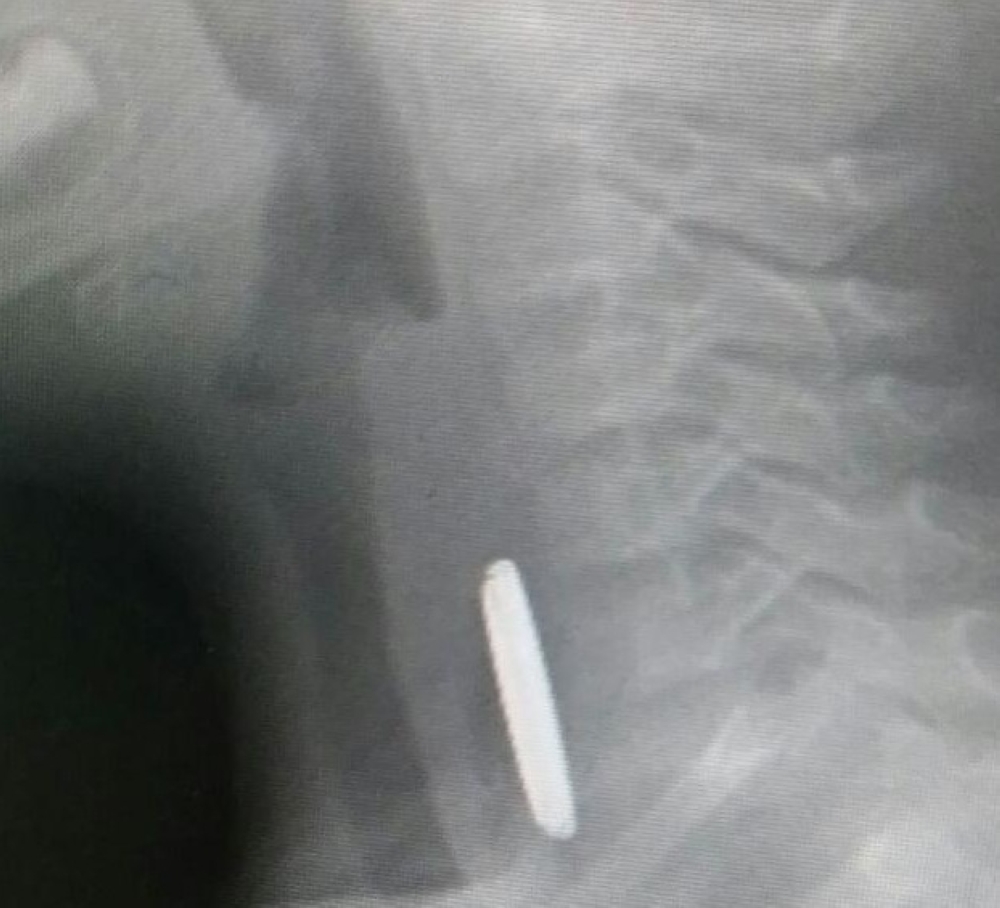

استقبل مستشفى خميس مشيط العام حالة محولة من مستشفى الملك عبدالله ببيشة لطفل يبلغ من العمر ثلاث سنوات قام ببلع بطارية ألعاب.

وبعد الكشف عليه واجراء التحاليل والأشعة، تم اجراء عملية ناجحة عاجلة للطفل عن طريق فريق طبي والتنسيق مع مستشفى الولادة والأطفال لتنويم الحالة حسب التنظيم الطبي المتبع.

استخراج بطارية ألعاب من مريء طفل